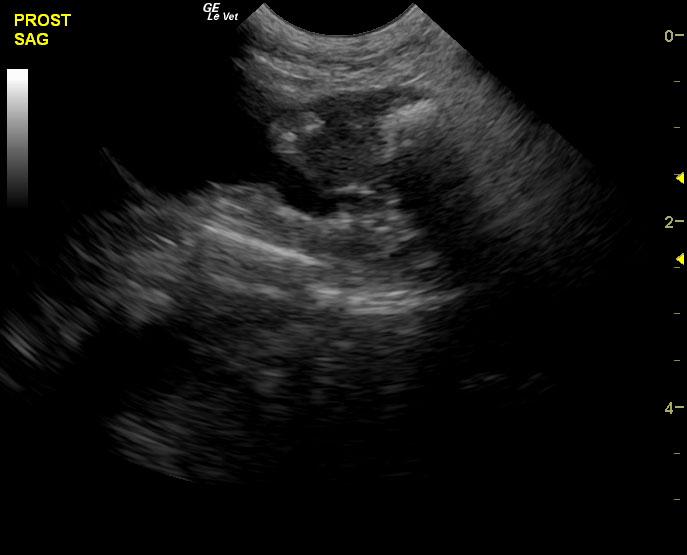

A 14-year-old neutered male Pomeranian dog was presented for evaluation of pollakiuria, diarrhea, inappetence, and lethargy. Abnormalities on physical examination included a painful, enlarged and symmetrical prostate, a very large and firm urinary bladder that could be expressed, and a grade III/VI heart murmur. On survey thoracic radiographs, calcification of the prostate gland was evident.